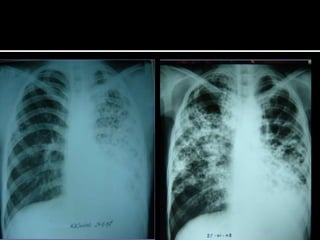

   Los hallazgos más frecuentes en la

tuberculosis primaria son las adenopatías y

las condensaciones

   La postprimaria las consolidaciones, los

nódulos y las cavidades, predominantes en

los segmentos apicales y posteriores de los

lóbulos superiores

   En algunos casos, sin embargo, es muy difícil

valorar si las lesiones radiológicas son activas

o no, especialmente si no se dispone de

estudios previos para comparar evolución

   En estos casos la TC y la TC de alta resolución

de tórax